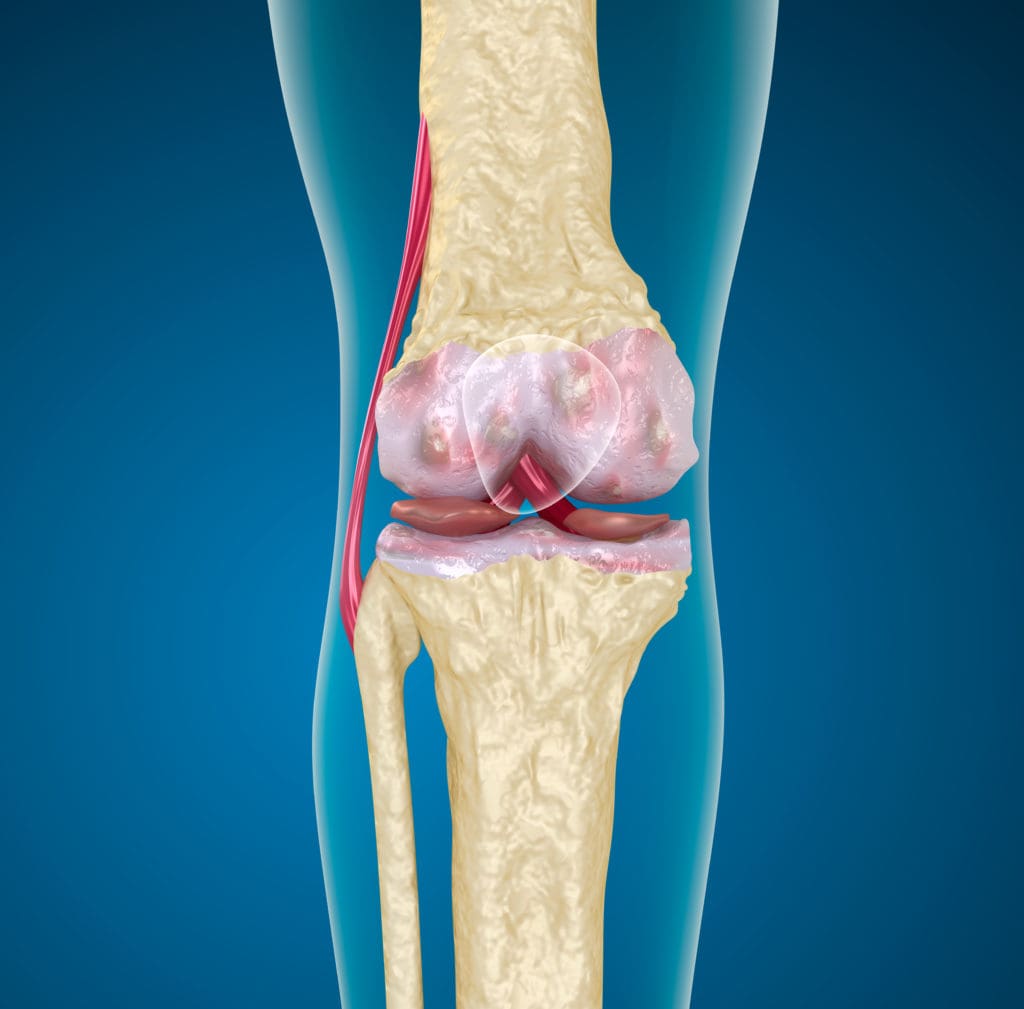

Медицинские снимки: рентген коленного сустава при остеопорозе